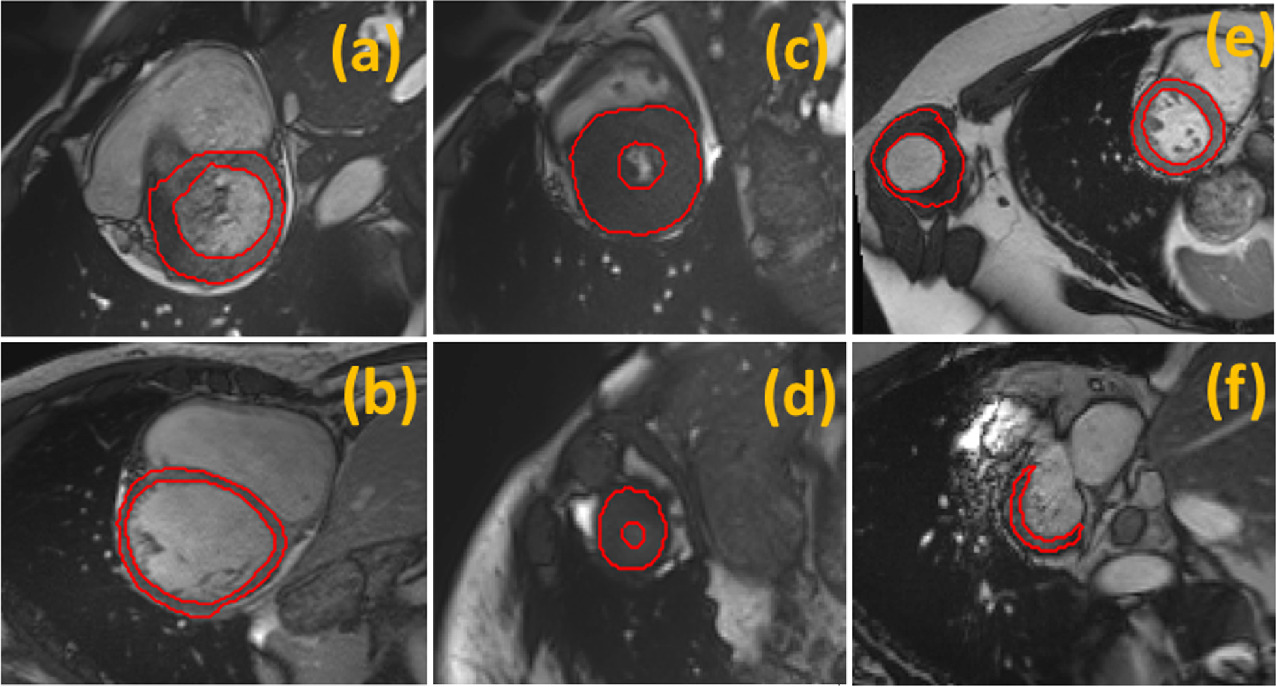

Multi-center, Multi-vendor, and Multi-disease Cardiac Image Segmentation Using Scale-Independent Multi-gate UNET

Heart segmentation in Cardiac MRI images is a fundamental step to quantify myocardium global function. In this paper, we introduce a pipeline for heart localization and segmentation that is fast and robust even in the apical slices that have small myocardium. Also, we propose an enhancement to the popular U-Net architecture for segmentation. The proposed method utilizes the aggregation of different feature scales from the image by using the inception block along with the multi-gate block that propagates the multi-scale context of the supplied data where the heart is subject to changes in scale